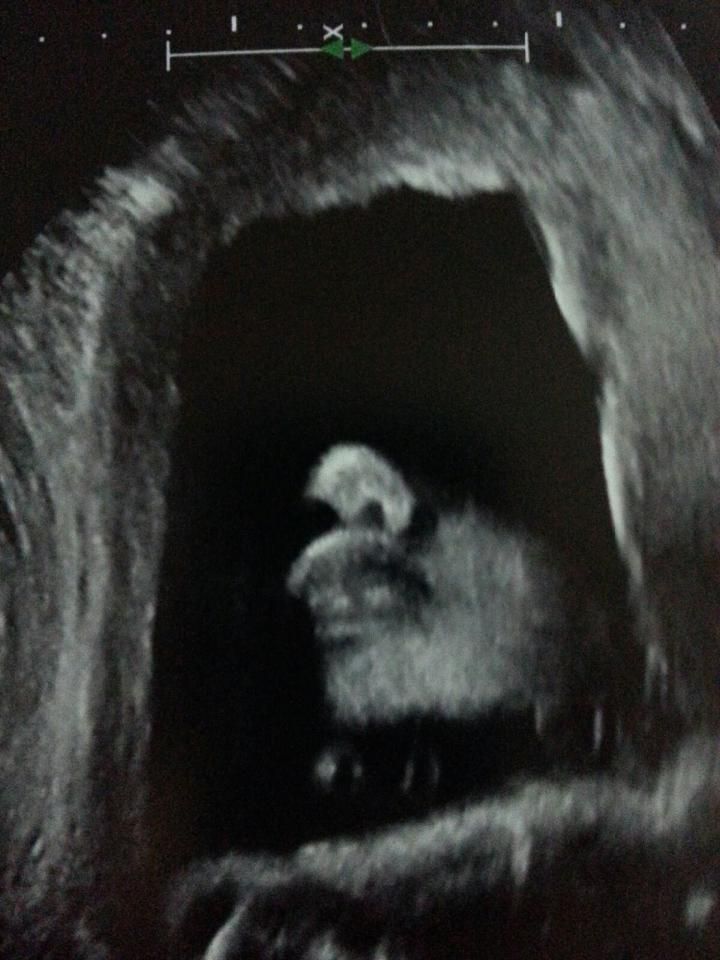

Month: <span>August 2013</span>